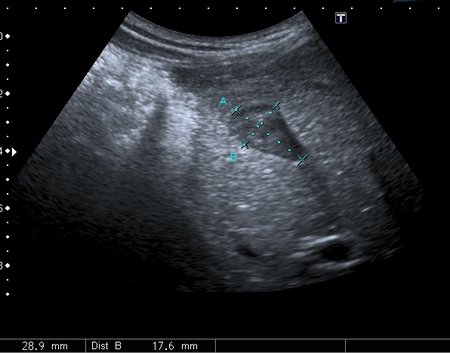

На УЗИ рядом с желчным пузырём определяется овоидное образование солидной струкутры с чёткими контурами.

Порекомендовал КТ, но в связи с наступающими новогодними праздниками и каникулами мальчик уехал домой и появился повторно через 2 месяца без жалоб для контрольного исследования. На УЗИ - картина осталась без динамики

Предположил наличие удвоения желчного пузыря, с этим заключением пациент исчез из поля зрения.

Полазил в сети на предмет удвоения желчного пузыря. Ультразвуковая картина значительно зависит от уровня, степени удвоения и оттока желчи из удвоенной части желчевыводящей системы. Вероятно в моём случае могло быть фундальное удвоение или V - образный желчный пузырь с нарушением оттока из латеральной половины с общим пузырным протоком. Сосудистый рисунок в печени и её воротах изменён не был. В любом случае хирурги лечить его не собирались - клиники не было. Хотя описаны случаи камнеобразования и опухолей ( почему - то невином) в удвоенном ЖП.Инга писал(а):А что с протоками? Я так предполагаю, что должно быть тоже некое удвоение (р.s я не утверждаю, я предполагаю, я с удвоением ЖП не сталкивалась)